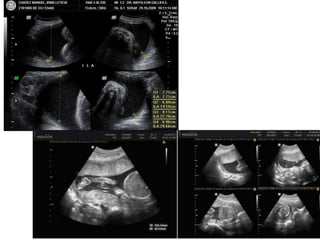

PERFIL BIOFISICO

• Consta de cinco variables biofísicas

• Integridad de la función cerebral fetal

(hipoxemia sistémica).

• Indicado en pacientes que presentan riesgo

perinatal.

• Tasa de falsos negativos: 0.6-0.8 ‰.

• Al menos un episodio de 30” de duración en 30 minutos.

Movimientos respiratorios fetales:

• Presencia de tres movimientos corporales o de las extremidades en 30 minutos.

Movimientos fetales:

• Al menos un episodio de extensión-flexión de piernas o tronco o apertura y cierre de

las manos en 30 minutos.

Tono fetal:

• Presencia de una ventana de líquido amniótico > 1 cm. Medida en dos planos

perpendiculares.

Volumen de líquido amniótico:

• Criterios del test basal.

Reactividad cardíaca fetal:

Cada parámetro se puntúa con un 2 si es normal o con 0 si es anormal. La puntuación

podrá oscilar entre 0 y 10.

PERFIL BIOFÍSICO MODIFICADO

• Dos variables:

– Reactividad de la FCF mediante un test basal.

– Índice de líquido amniótico (la suma en

centímetros de cuatro lagunas de líquido

amniótico): Normal 6 a 25cm.

• Frecuencia de falsos negativos es del 0,8 ‰, falsos

positivos 60%. Necesita pruebas de respaldo.